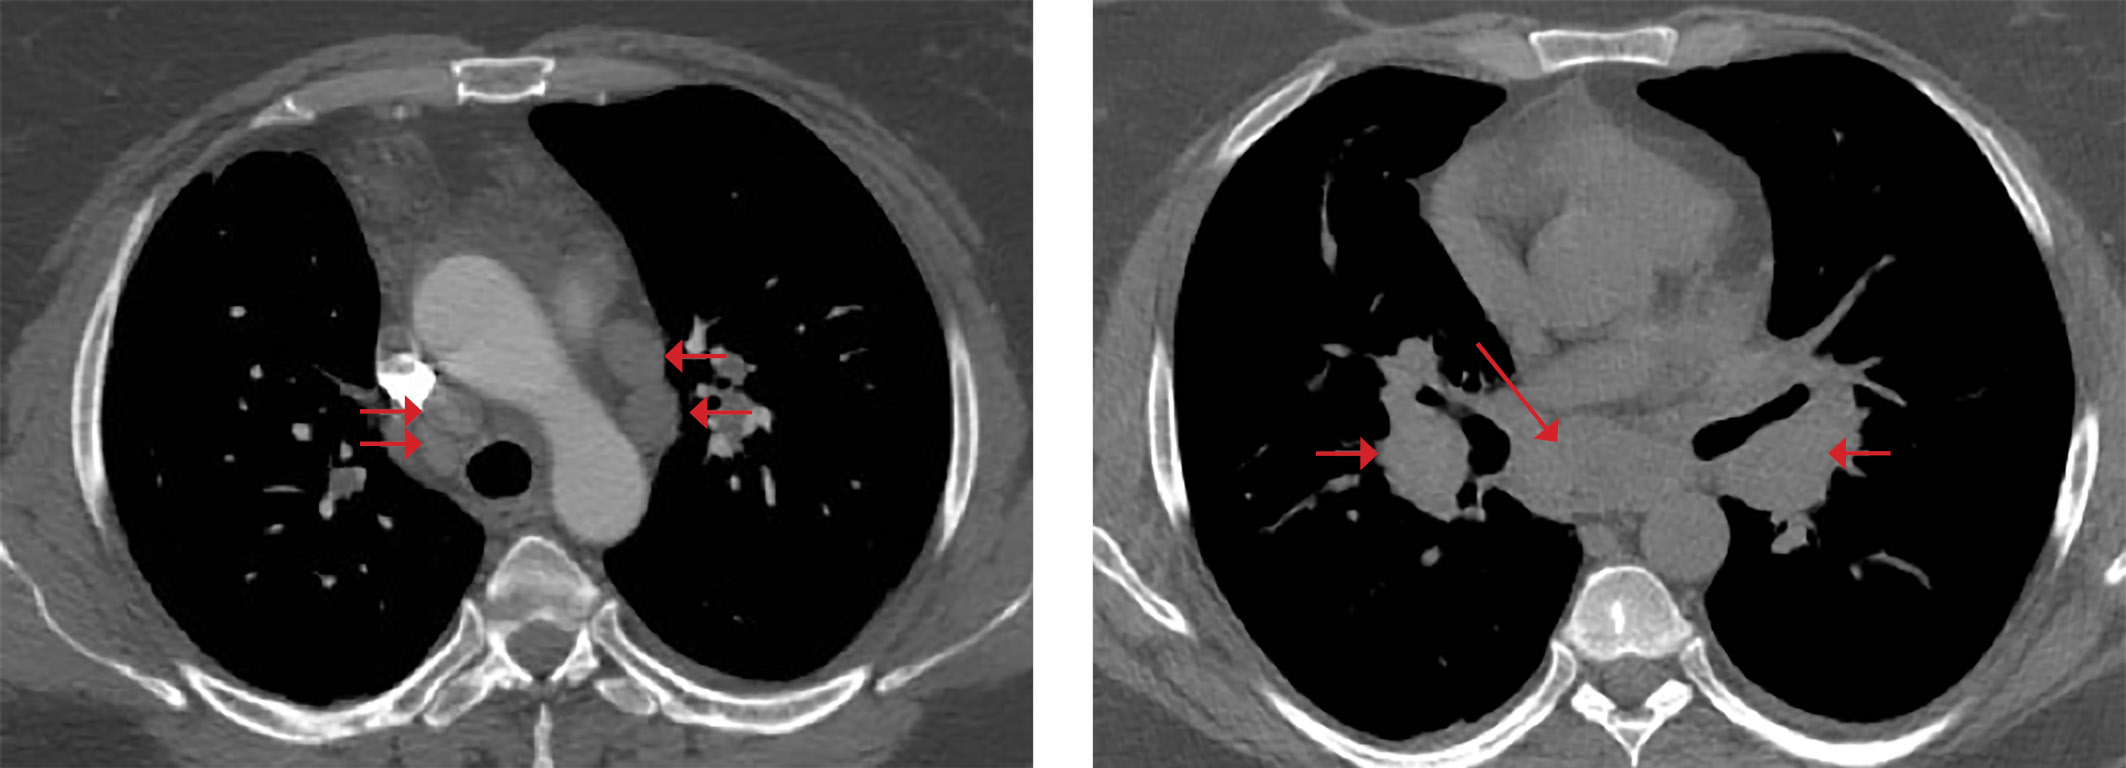

При КТ органов грудной клетки (рис. 2, 3) выявлены множественные мелкоочаговые затемнения в легочной паренхиме лимфогенного распределения, немногочисленные ретикулярные затемнения, уплотнение перибронховаскулярного интерстиция и увеличение лимфоузлов средостения и корней легких, т.е. симптомокомплекс, высокоспецифичный для острой формы саркоидоза. Лабораторные данные подтвердили активность системного воспаления: скорость оседания эритроцитов (СОЭ) 42 мм/ч (0–20), уровень С-реактивного белка (СРБ) был повышен до 7,23 мг/л (норма 0,01–4,99). Уровень кальция крови был в пределах нормальных значений. Проводилась дифференциальная диагностика с туберкулезом органов дыхания и лимфопролиферативными заболеваниями, результаты обследования пациентки и оценка течения заболевания позволили исключить эти заболевания.

Рисунок 2. Саркоидоз легких и внутригрудных лимфоузлов у пациентки М.

Невыраженное уплотнение перибронховаскулярного интерстиция

(указано стрелкой).

Рисунок 3. Увеличение внутригрудных лимфоузлов

как проявление саркоидоза у пациентки М.

Учитывая наличие типичной клинико-рентгенологической симптоматики острого течения саркоидоза и отсутствие данных за другие возможные причины поражения легких, морфологическую верификацию диагноза не проводили. Жалобы на мышечную слабость и тошноту у пациентки после недавней аденомэктомии по поводу болезни Иценко–Кушинга были расценены как декомпенсация надпочечниковой недостаточности вследствие присоединившегося системного воспаления. Доза гидрокортизона увеличена до 25 мг/сут (10 мг утром, 10 мг в обед и 5 мг вечером), на фоне которой тошнота и слабость прекратились. В дальнейшем, в течение нескольких месяцев отмечалось постепенное исчезновение узловатой эритемы. При динамической КТ органов грудной клетки, выполненной через год после диагностики саркоидоза, очаговые тени и увеличение внутригрудных лимфоузлов сохранялись, но не прогрессировали, что косвенно подтвердило диагноз саркоидоза; отмечалась положительная динамика показателей СОЭ и СРБ. Пациентка продолжала прием гидрокортизона в дозе 25 мг/сут. В дальнейшем связь с пациенткой оборвалась в связи со сменой места жительства.

Синдром Лефгрена предполагает наличие симптомокомплекса, включающего узловатую эритему, артриты, повышение температуры и рентгенологические изменения в виде внутригрудной лимфаденопатии [20]. На КТ органов грудной клетки при синдроме Лефгрена возможна визуализация поражения легочной паренхимы вследствие ее вовлечения при саркоидозе. Наряду с характерным для синдрома Лефгрена увеличением внутригрудных лимфоузлов, на КТ легких у нашей пациентки выявлялись интерстициальные изменения в легочной паренхиме (мелкоочаговые и ретикулярные тени), не исчезнувшие в течение более 1 года, что свидетельствует в пользу трансформации острой формы саркоидоза в хроническую [20]. Лабораторные тесты при синдроме Лефгрена выявляют признаки повышения острофазовых показателей воспаления в крови (СОЭ, СРБ). Показатели функции внешнего дыхания, легочной диффузии, результаты тестов толерантности к нагрузке при синдроме Лефгрена, как правило, соответствуют нормальным показателям и не являются методом диагностики заболевания, поэтому эти исследования у данной пациентки не проводились.